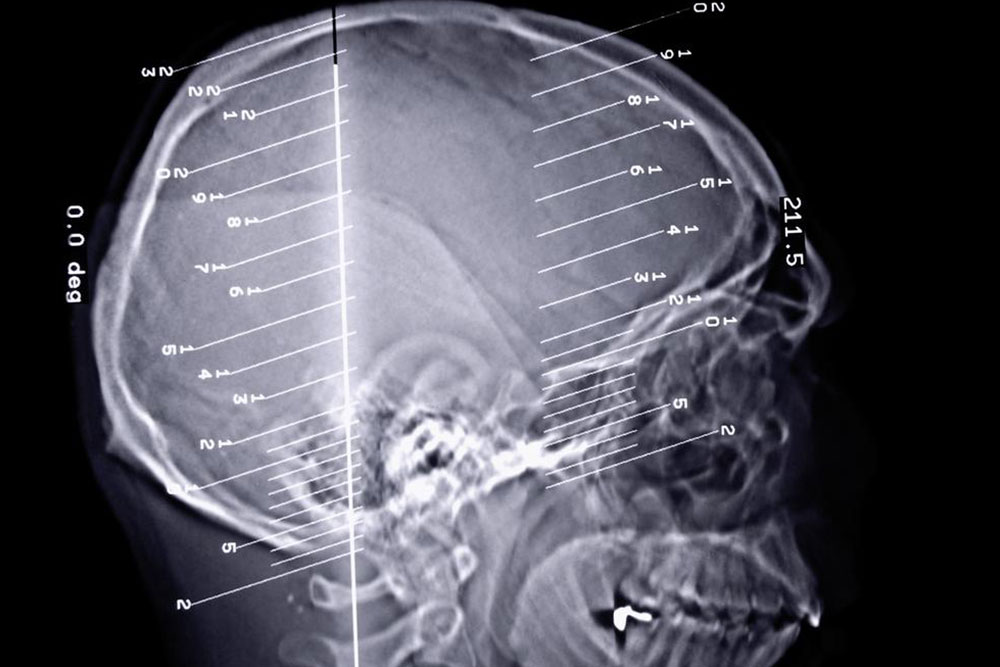

The human body can perform all its functions seamlessly when every organ of the body works in unison to perform the task. A slight change in the functions of the organ can disrupt the entire functioning of the body. Epilepsy seizures are a kind of disorder that occurs when we there is a problem in our brain’s electrical system.